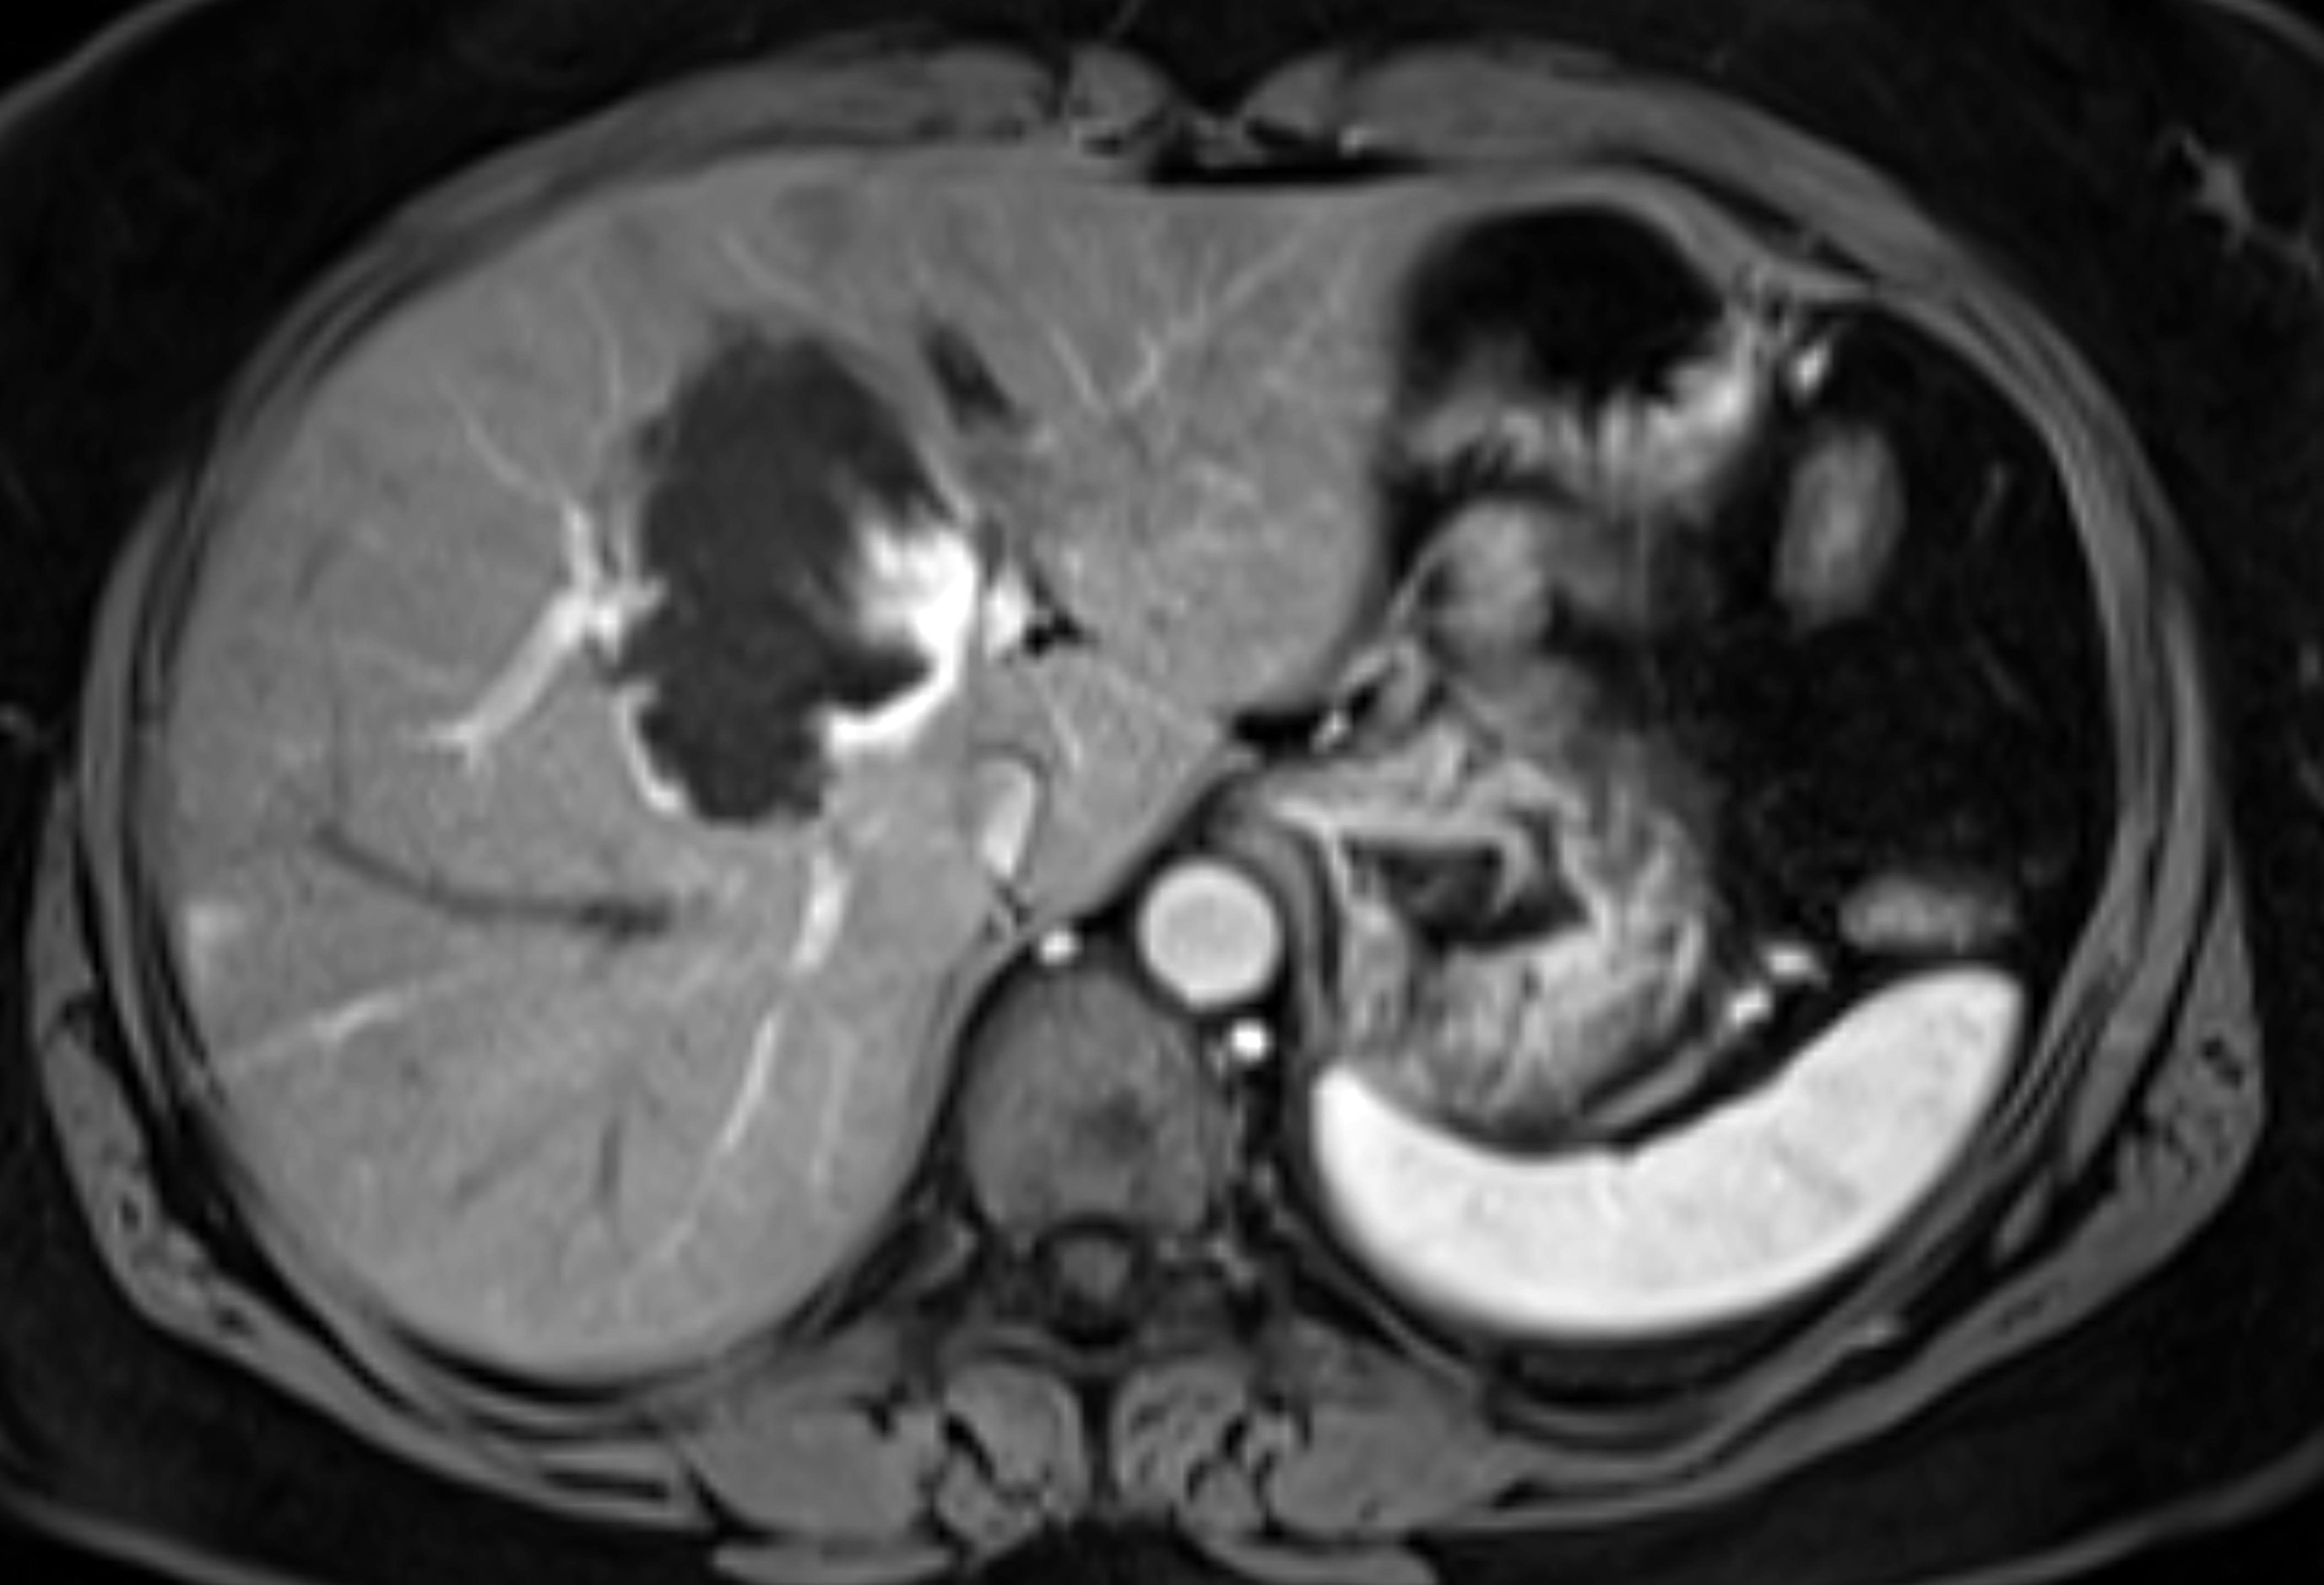

How They Did It — The researchers injected lab mice with hepatocellular carcinoma cells, a common type of liver cancer known to be drug-resistant.

Abstract: Cancer cells voraciously consume nutrients to support their growth, exposing metabolic vulnerabilities that can be therapeutically exploited. Here, we show in hepatocellular carcinoma (HCC) cells, xenografts, and patientderived organoids that fasting improves sorafenib efficacy and acts synergistically to sensitize sorafenib-resistant HCC. Mechanistically, sorafenib acts noncanonically as an inhibitor of mitochondrial respiration, causing resistant cells to depend on glycolysis for survival. Fasting, through reduction in glucose and impeded AKT/mTOR signaling, prevents this Warburg shift. Regulating glucose transporter and proapoptotic protein expression, p53 is necessary and sufficient for the sorafenib-sensitizing effect of fasting. p53 is also crucial for fasting-mediated improvement of sorafenib efficacy in an orthotopic HCC mouse model. Together, our data suggest fasting and sorafenib as rational combination therapy for HCC with intact p53 signaling. As HCC therapy is currently severely limited by resistance, these results should instigate clinical studies aimed at improving therapy response in advanced-stage HCC.